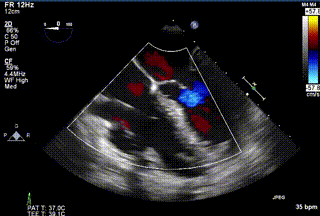

2021年12月24日,復(fù)旦大學(xué)附屬中山醫(yī)院葛均波院士團(tuán)隊(duì)成功應(yīng)用LuX-Valve Plus為一例極重度三尖瓣反流(TR)合并房顫、房缺的患者完成了經(jīng)血管三尖瓣置換術(shù),這是在前基礎(chǔ)上,本周完成的第三例經(jīng)血管三尖瓣置換手術(shù),葛均波院士、周達(dá)新教授等與心外科魏來(lái)教授、賴顥教授,心超室的潘翠珍教授、李偉教授及麻醉科的郭克芳教授共同完成了本周手術(shù),均獲得圓滿成功!患者術(shù)后超聲顯示無(wú)TR,臨床癥狀明顯改善。本周手術(shù)的成功也為L(zhǎng)uX-Valve Plus救治性臨床研究添上了濃墨重彩的一筆。

三例患者入院后,葛均波院士團(tuán)隊(duì)周達(dá)新教授、潘文志教授、張?jiān)床┦?、陳莎莎博士及心超室的潘翠珍教授、李偉教?/strong>對(duì)患者的情況進(jìn)行詳細(xì)評(píng)估和討論,最終決定為三例患者選擇LuX-Valve Plus40mm、50mm和50mm型號(hào)的瓣膜進(jìn)行手術(shù)治療。手術(shù)后即刻拔除氣管插管,術(shù)后患者三尖瓣反流癥狀得到顯著改善,復(fù)查心超結(jié)果顯示人工三尖瓣瓣膜支架固定穩(wěn)定,瓣葉關(guān)閉形態(tài)未見(jiàn)異常,未見(jiàn)明顯反流。